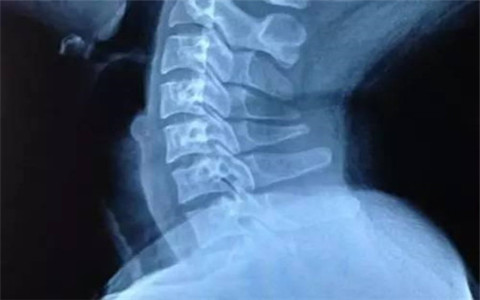

頸椎病是日常生活中常見(jiàn)的一種疾病,尤其近幾年來(lái)發(fā)病率逐年升高,讓人不得不重視。那么它有哪些癥狀呢,又有哪些臨床表現(xiàn)呢,今天帶大家了解一下,幫助大家自我判斷一下是否患上了頸椎病。

頸椎病是由于頸椎間盤(pán)發(fā)生退行性改變及繼發(fā)性改變后刺激或壓迫頸神經(jīng)根、頸部脊髓、椎動(dòng)脈、頸部交感神經(jīng)而引起的各種癥狀和體征。常見(jiàn)于中老年人和長(zhǎng)期坐辦公室工作的年輕人。